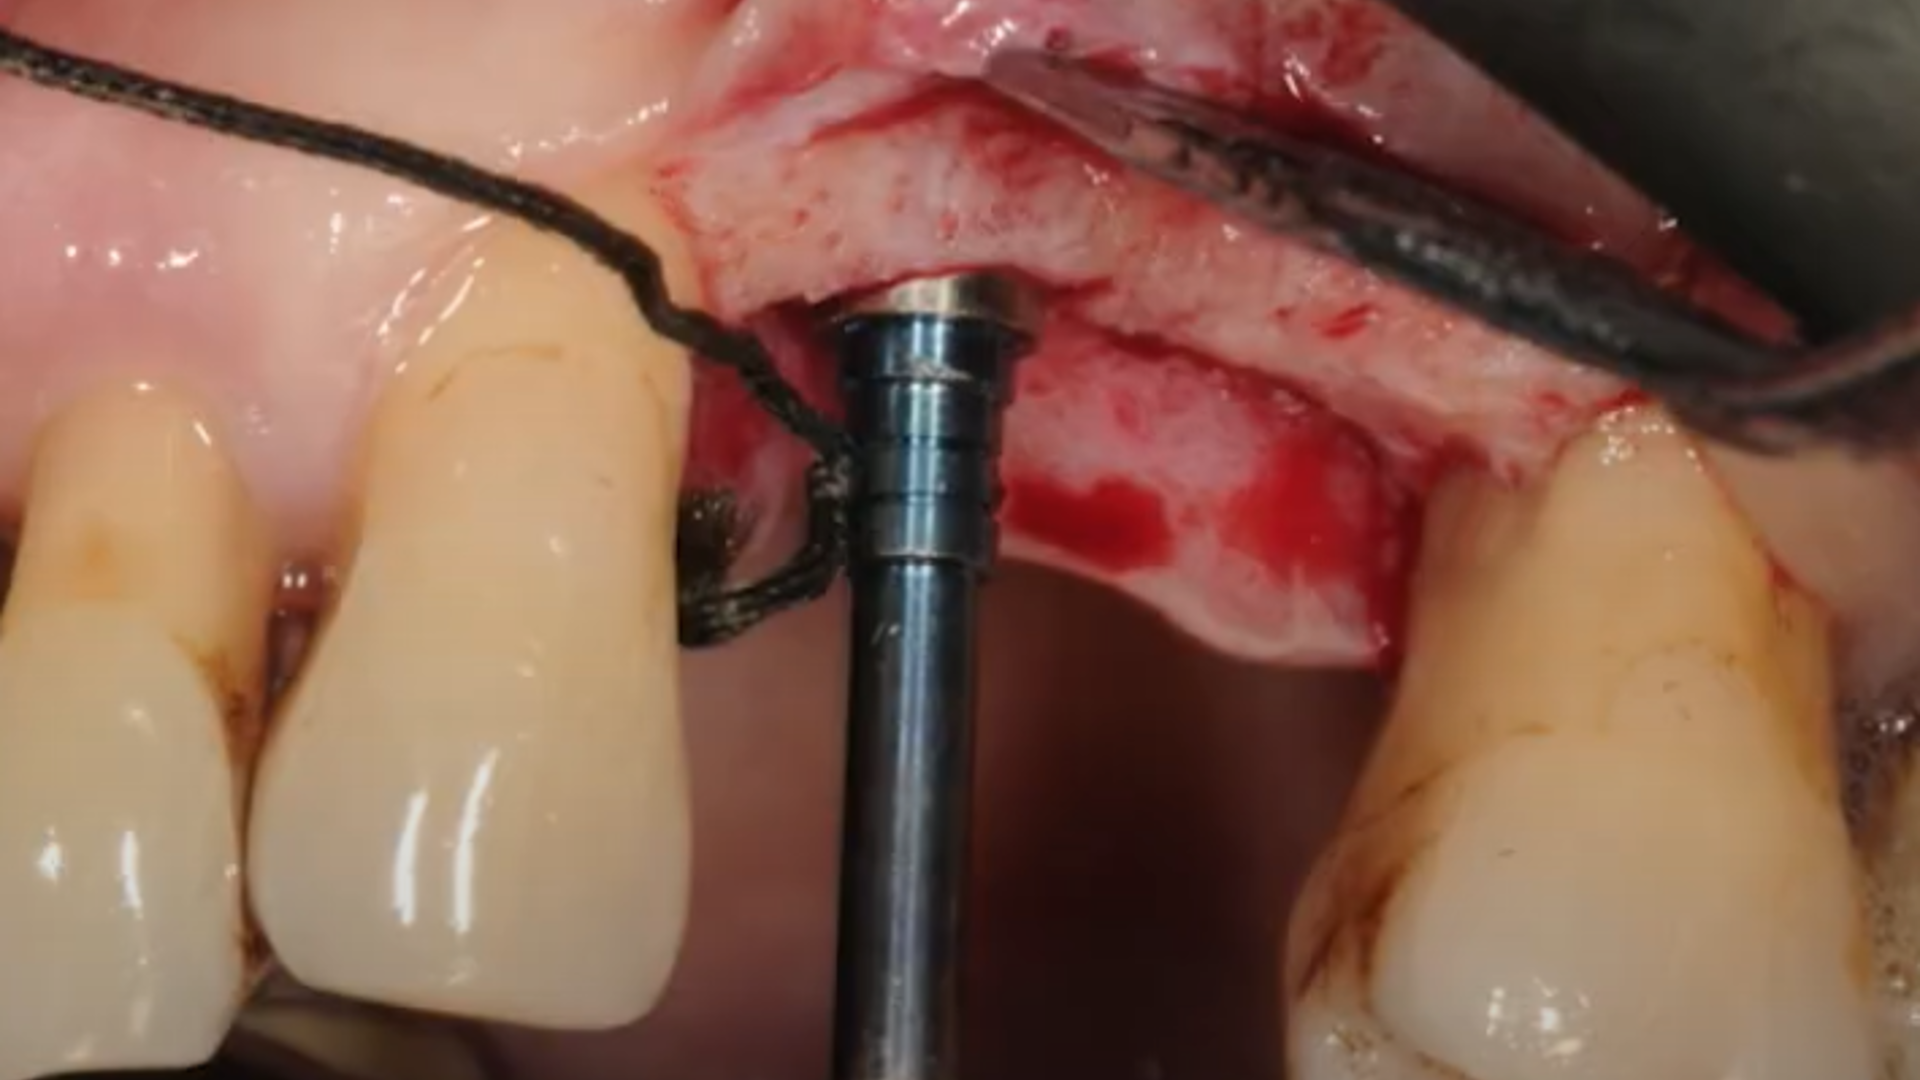

The evolution of the Lateral Approach: Lateral Window and Simplified Antrostomy Design

Evolution of sinus lift procedures: Piezo Surgery and Osseodensification

Example of different clinical cases: step-by-step surgical protocol

Osseodensification technique